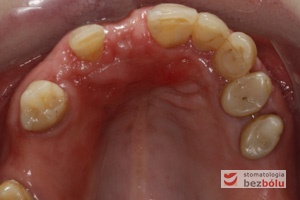

Obraz kliniczny przed ekspozycją implantu - wyrostek zębodołowy 3 miesiące po implantacji przygotowany do odsłonięcia implantu

Obraz kliniczny przed ekspozycją implantu – wyrostek zębodołowy 3 miesiące po implantacji przygotowany do odsłonięcia implantu